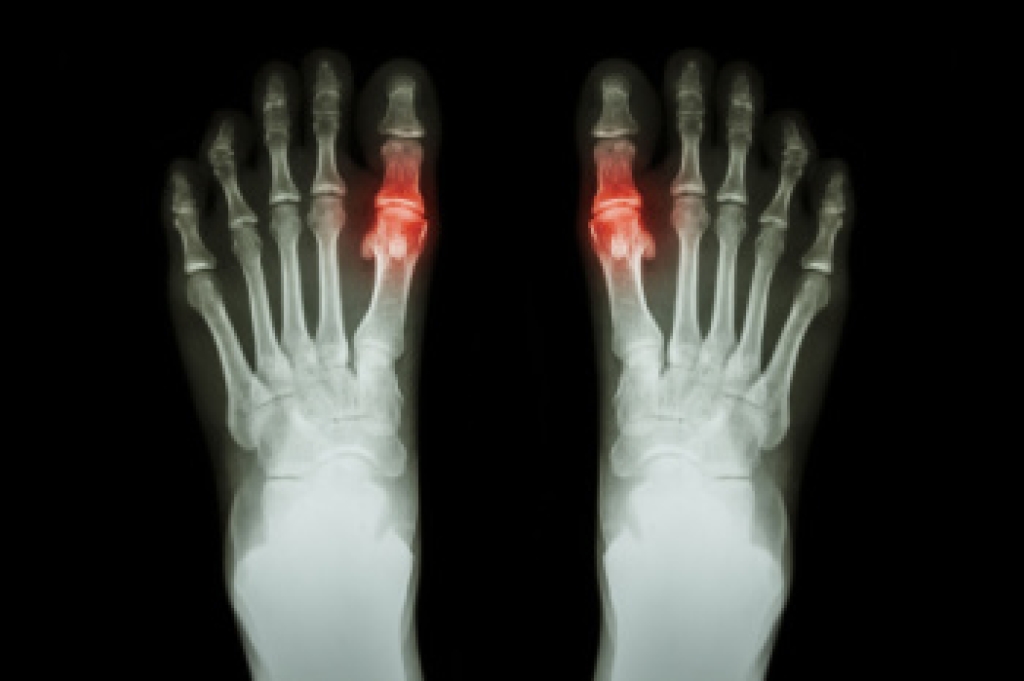

Diabetes affects millions of people every year. The condition can damage blood vessels in many parts of the body, especially the feet. Because of this, taking care of your feet is essential if you have diabetes, and having a podiatrist help monitor your foot health is highly recommended.